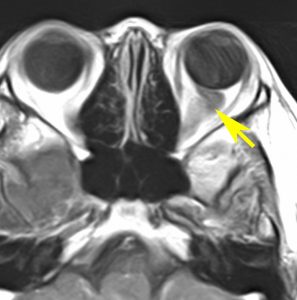

眼窩内単視神経膠腫

1歳児の左眼窩内単視神経膠腫です。左目は手動弁程度ですから,全摘出しました。まぶたの動きと眼球運動は温存しました。この例に何年も化学療法を続けるのは馬鹿げています。

左の写真は,左眼窩内腫瘍,右の写真は,頭蓋内の正常左視神経です。